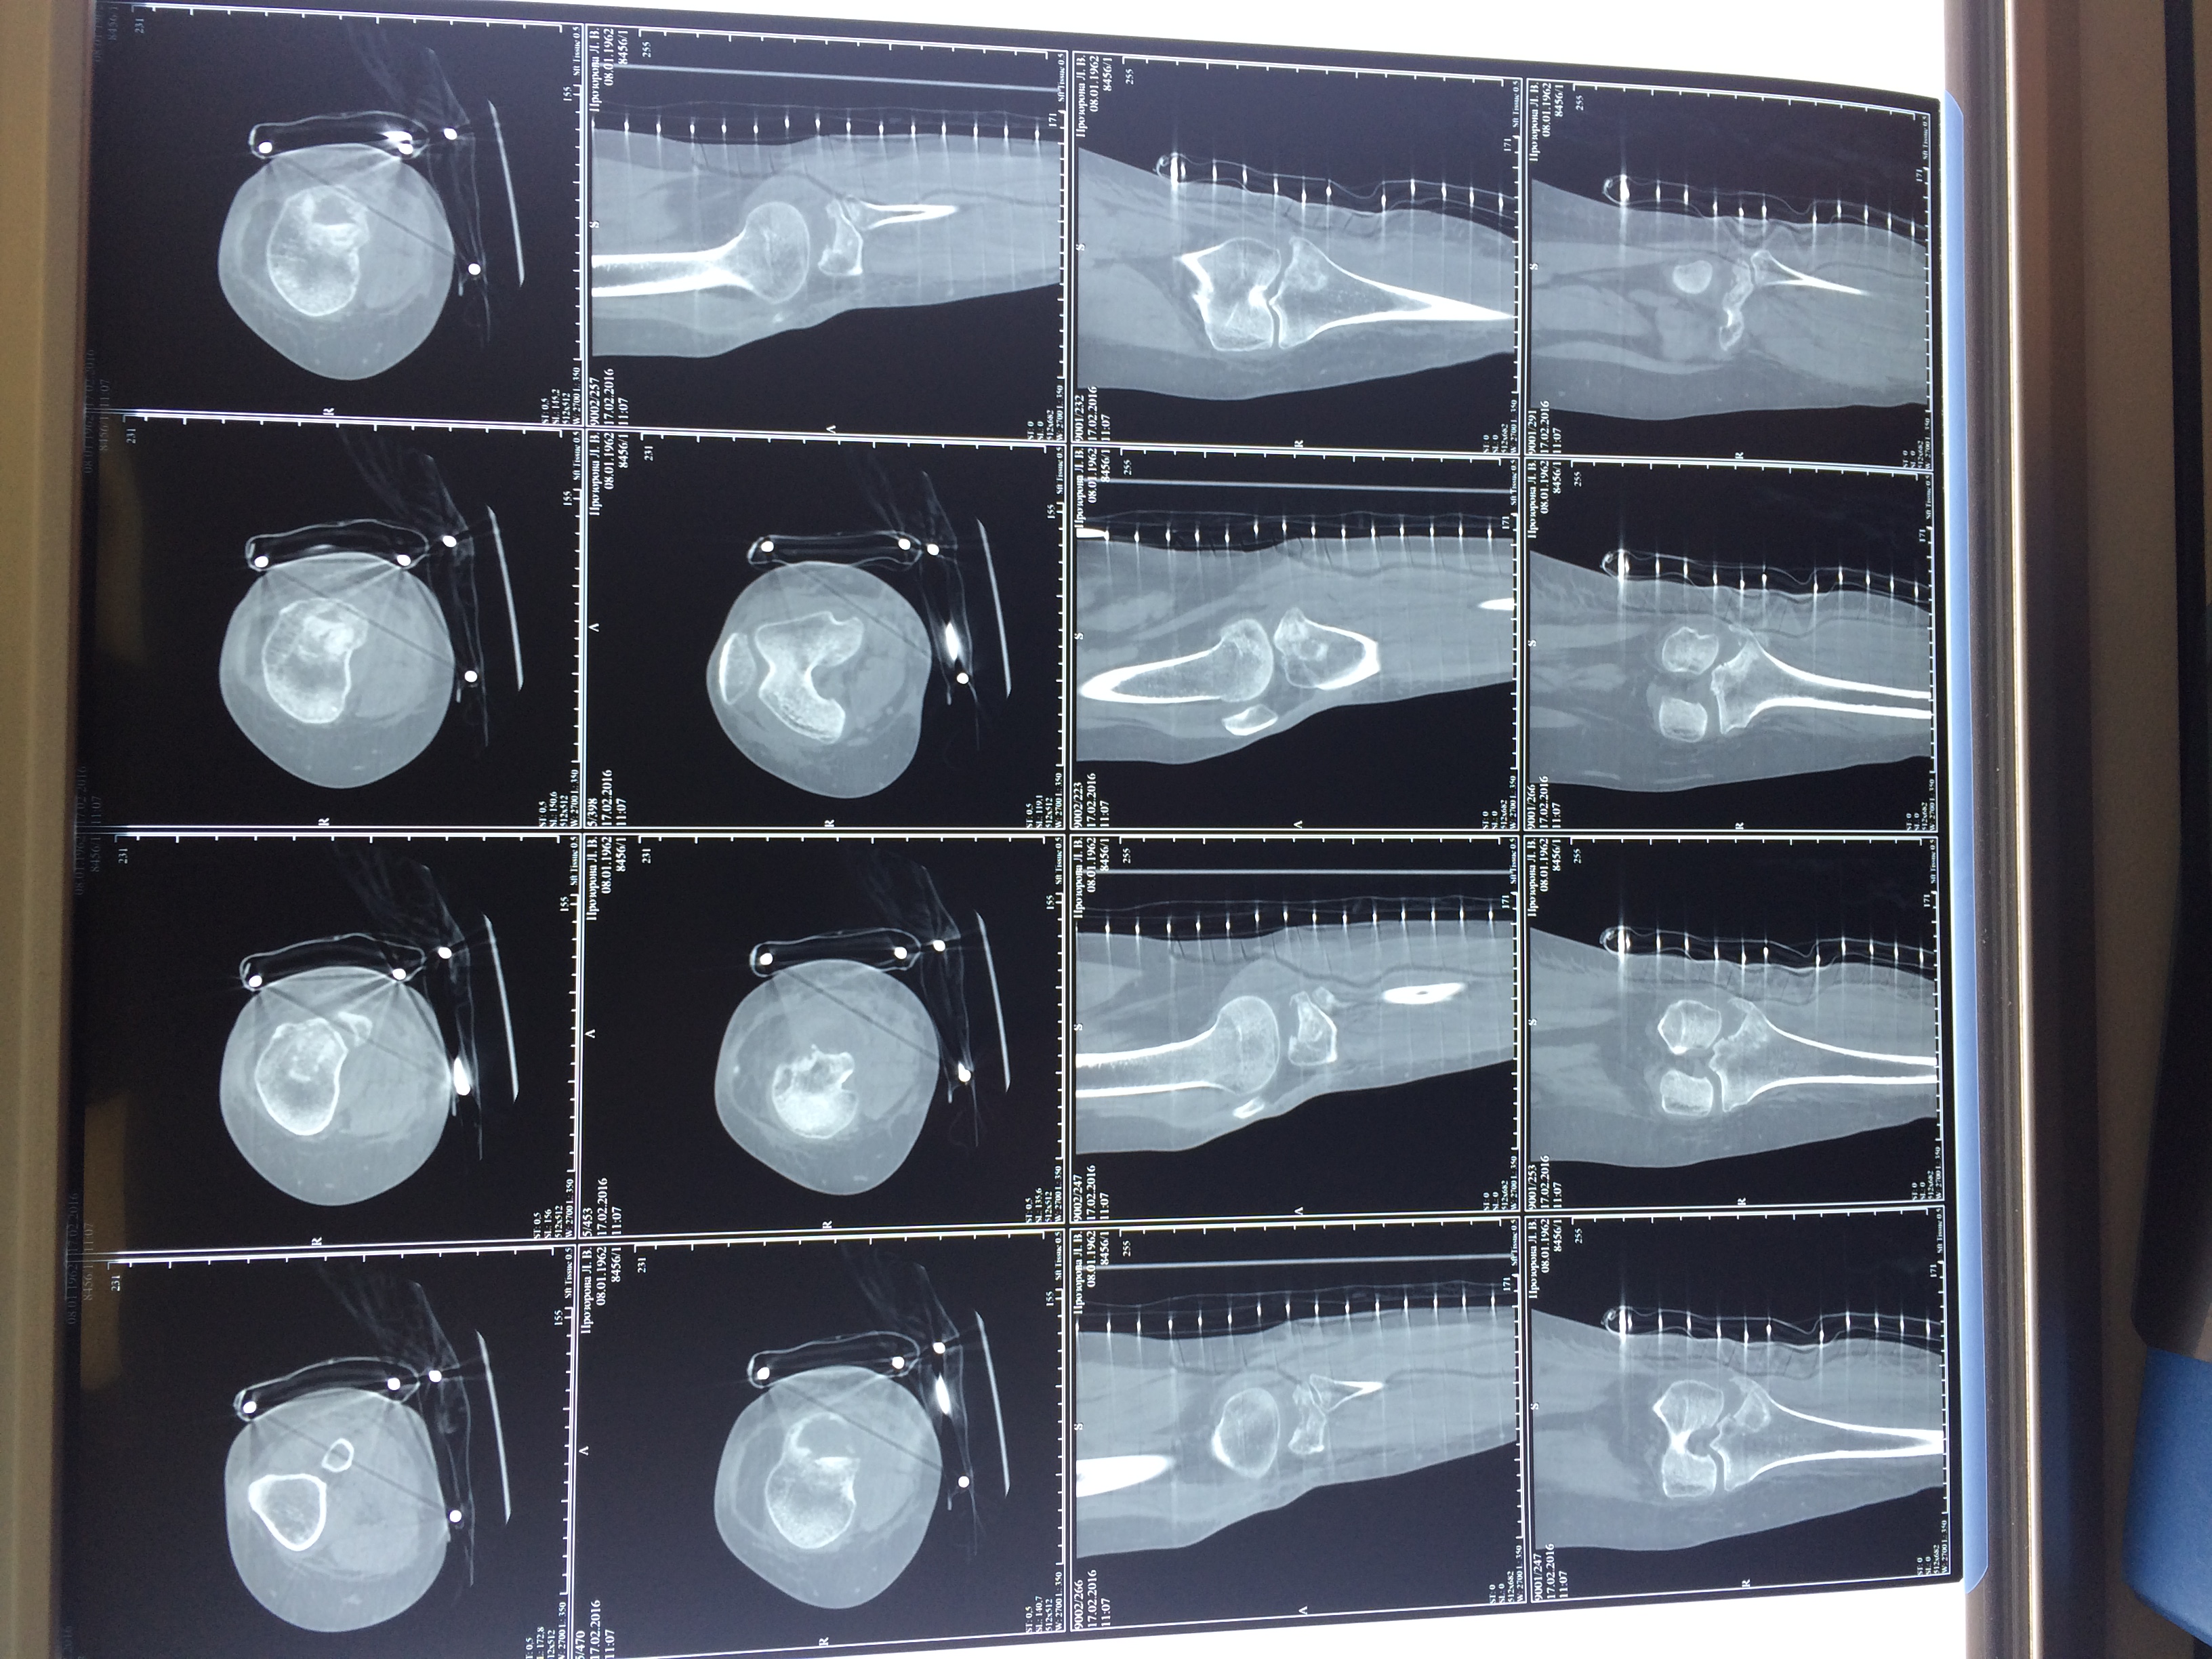

Использование материала Остеоматрикс при импрессионном оскольчатом переломе наружного мыщелка большеберцовой кости по типу Schatzker II

Использование материала Остеоматрикс при импрессионном оскольчатом переломе наружного мыщелка большеберцовой кости по типу Schatzker II.